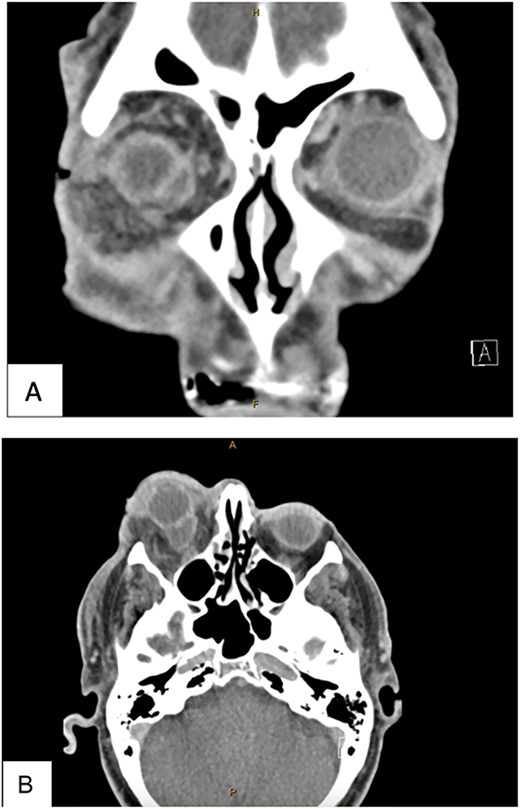

The patient underwent transconjunctival peritomy and drainage of the inferomedial abscess. However, vision regressed from hand movements to no light perception 5 days following initial drainage. Re-imaging of the orbit revealed a new retroorbital abscess accumulation superior-temporally (Fig. 4) that was also then drained. Both collections contained frank pus, and cultures also grew methicillin sensitive S. aureus, requiring a prolonged course of intravenous flucloxacillin and oral steroids. Subsequent MRI showed right lateral retroorbital abscess regression and less prominent retroorbital phlegmonous changes (Fig. 5). However, vision did not return to the patient’s eye.

Axial (A) and coronal (B) MRI T1 FS post contrast imaging demonstrating new, right sided posterosuperior, peripherally enhancing collection post drainage of previous collection.